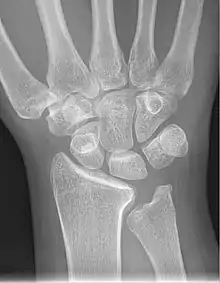

Left hand x-ray with Kienbock's Disease showing 4 mm negative ulnar variance and Kienbock's Disease Stage IIIB

Left hand x-ray with Kienbock's Disease